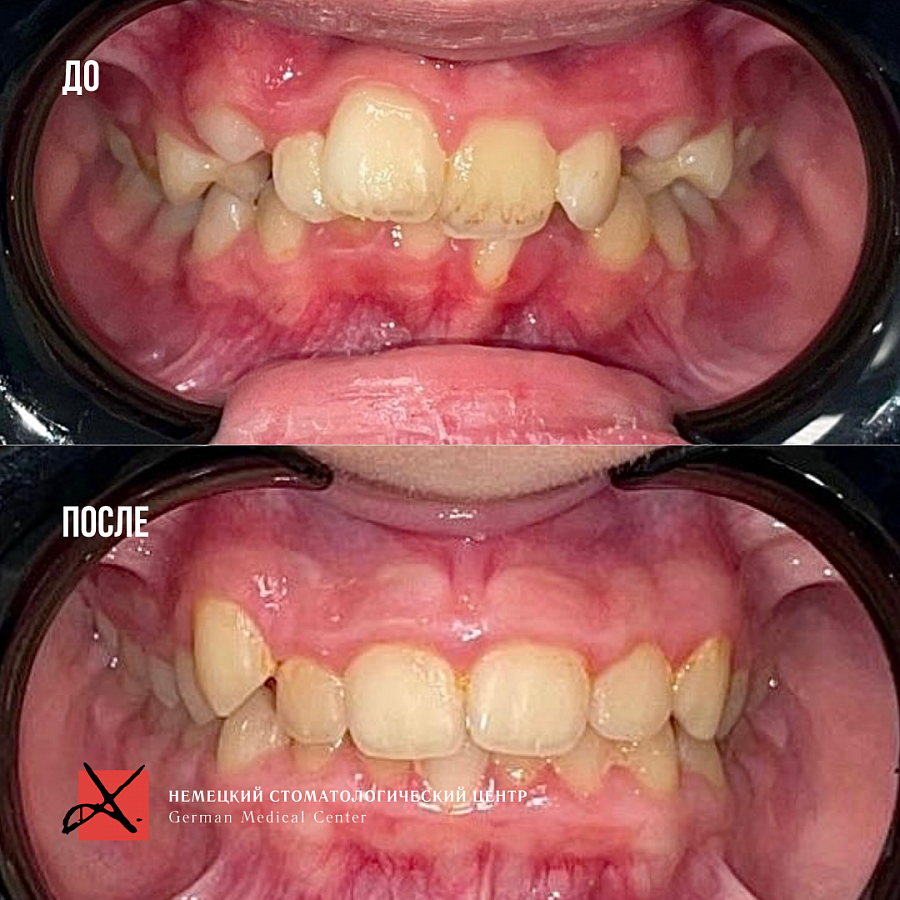

Исправление прикуса у 9-летней пациентки

Пациентке 9 лет. Имеется ряд проблем:

- ротация верхней челюсти

- скученное положение зубов

- глубокая окклюзия

- Провели работу на функциональном аппарате, увеличивающем объем костной ткани верхней челюсти

- На нижнюю челюсть поставили расширяющую пластинку.

Изменения отлично видны на фото: положение зубов значительно изменилось. Зубки теперь растут ровными рядами.